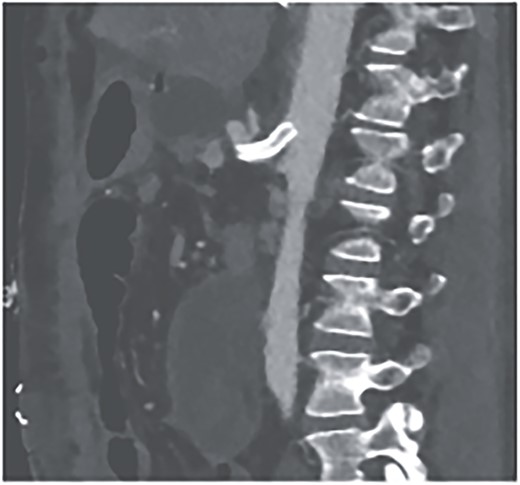

Postoperatively, the patient achieved hemodynamic stabilization in the intensive care unit. On the sixth postoperative day, there was a recurrence of circulatory collapse in addition to relevant bloody discharge through the drains. CT imaging once again revealed an active bleeding of the pancreaticoduodenal artery, which was successfully treated interventionally using coiling (Figs 2 and 3).

Angiography revealing the aneurysm of the pancreaticoduodenal arcade.